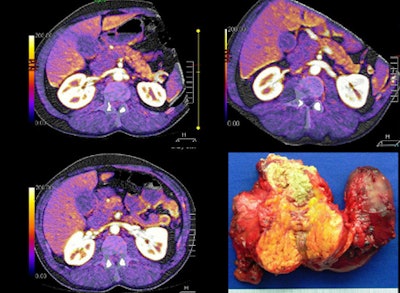

| Large pancreatic mass and head are visible at perfusion CT, with surgery specimen for comparison. |